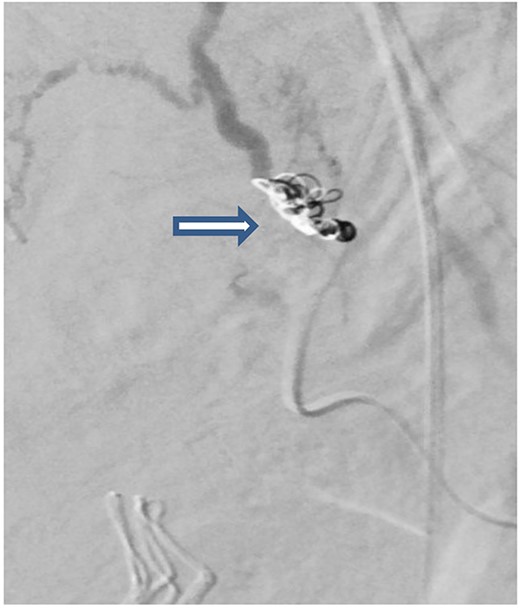

The case was again discussed between trauma and obstetric teams for possible need for interventional radiology consultation. Angiogram showed tortuous arteries with parenchymal blush in the right side of uterine wall, which was related to postpartum status. Gelfoam embolization of the right uterine artery was done to reduce the flow. On the other side, angiogram detected a pseudoaneurysm measuring ~7 mm (Fig. 3). Multiple vortex coils were used to obliterate the feeding vessels and post embolization angiogram showed satisfactory results (Fig. 4).

Pelvic angiogram revealed a pseudoaneurysm (see arrow) measuring ~7 mm arising from the branches of the left uterine artery.

Post embolization angiogram showed satisfactory results after multiple Vortex coils were used to obliterate of feeding vessels.